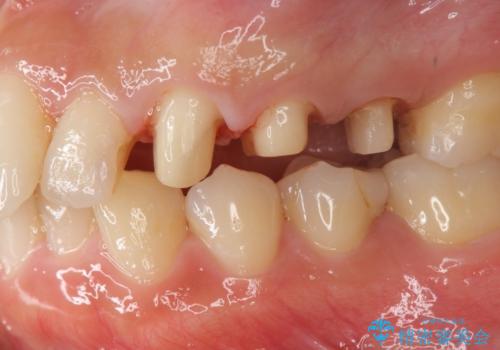

- 歯ぐきの腫れや、歯の内部が黒く見えることからの虫歯の治療を求めて来院されました。

虫歯が大きかったことから、神経の温存はできたものの歯ぐきよりも深い虫歯の問題を解決するため部分矯正治療を併用したセラミック治療を行うこととしました。